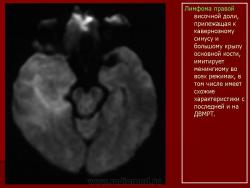

Лимфомы головного мозга.